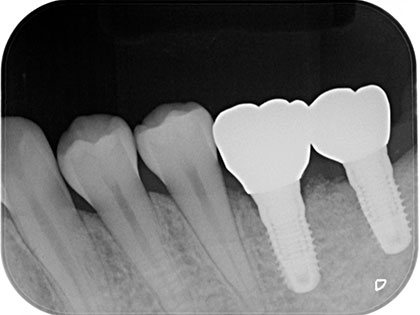

左下6が噛むと痛いため、インプラント治療を希望された患者様の症例になります

左下6が噛むと痛く、7に歯をいれたいためインプラントを希望との事で来院

初診時の写真がこちら

治療中の写真がこちら

治療完了時の

写真がこちら

左下6を他院で治療後、噛むと痛い歯が破折した事で抜歯と同時に骨造成をしました。

骨が出来上がるのに4か月程待つ間に、左下親知らずが水平埋伏しており、7番目にインプラントを埋入するにあたり左下親知らずが残ったままでは汚れがたまり、結果的にインプラントもダメになる可能性があるため、親知らずを抜歯後にインプラントを埋入しました。